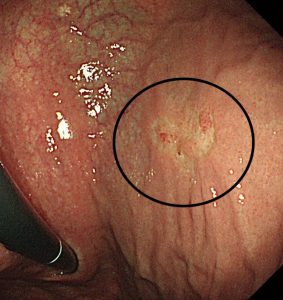

続いて内視鏡画像を提示します。

生検の結果分化型 tub が検出されました。